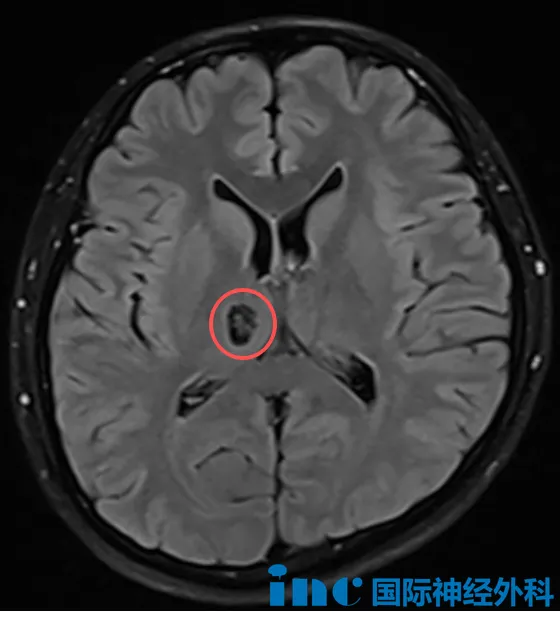

一次常规体检,28岁的孙先生意外发现右侧丘脑存在一个14mm×10mm的占位,虽然目前无任何神经功能症状,但颅内这个“不速之客”却让他陷入两难:无症状的脑部占位究竟该如何应对?何时才是手术的最佳时机?

面对这个常见却令人困惑的问题,巴教授基于丰富的临床经验,指出目前主要有两种方向:

1、积极明确:直接手术切除

“如果选择手术,目标是实现肿瘤全切。事实上,我们过去的许多病例已证明,这类手术是可以实现的。当然,手术的难度在于,这类病变可能在术中没有肉眼可辨的清晰边界,但全切仍是明确诊断并争取良好预后的关键。”

2、观察:定期影像随访

“另一种选择是定期进行核磁共振检查,密切观察这个病灶是否有变化。如果随访中发现占位体积增大,那么通常建议尽早手术干预。”